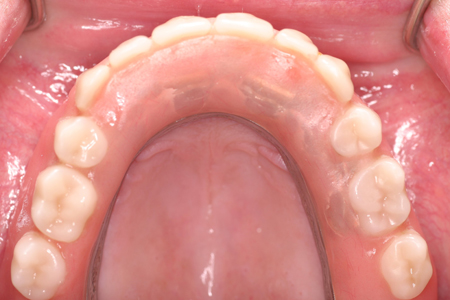

Er zijn 5 implantaten met een staaf/huls constructie geplaatst in de bovenkaak.

![overkappingprothese3[1].jpg overkappingprothese3[1].jpg](https://www.implantologie-vanderkroft.nl/storage/images/5cb72a79cbfab_overkappingprothese3-1.jpg)

De bovenprothese wordt vastgeklikt op de staaf/hulsconstructie,

de prothese zit heel goed vast en het gehemelte is onbedekt.